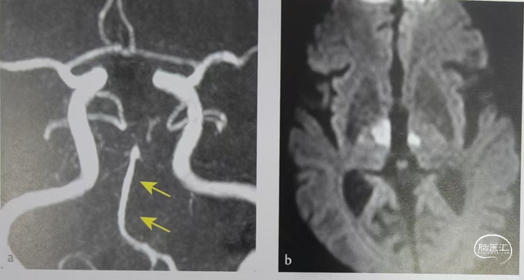

DWI显示双侧丘脑穿支动脉梗塞。MRI显示基底动脉纤细,远端无大脑后动脉,双侧大脑后动脉通过颈内动脉供血,因为无血管出路,基底动脉纤细。

左侧椎动脉造影显示双侧PCA均未显影,双侧小脑上动脉(SCA)显影清晰和丘脑穿支动脉(黄色箭头)可见造影剂充盈。左侧颈内动脉造影同侧大脑后动脉显影(箭头)。丘脑梗塞为颈内动脉发出后交通远端供血血管梗塞。

特别注意:不要将P1段胚胎型缺如或发育不良误判为P1段急性闭塞。不适合进行取栓。